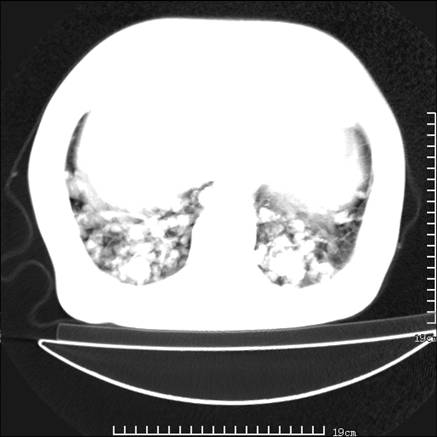

张男,75岁,干咳半年余,小便不利二年,b超检查前列腺增大,未见明显肿块;前列腺癌血生化检查多项指标明显增高。

双肺内多发转移瘤,纵膈淋巴结转移。来源前列腺?建议盆腔mri进一步检查。

双肺转移满了。

两肺广泛转移瘤。